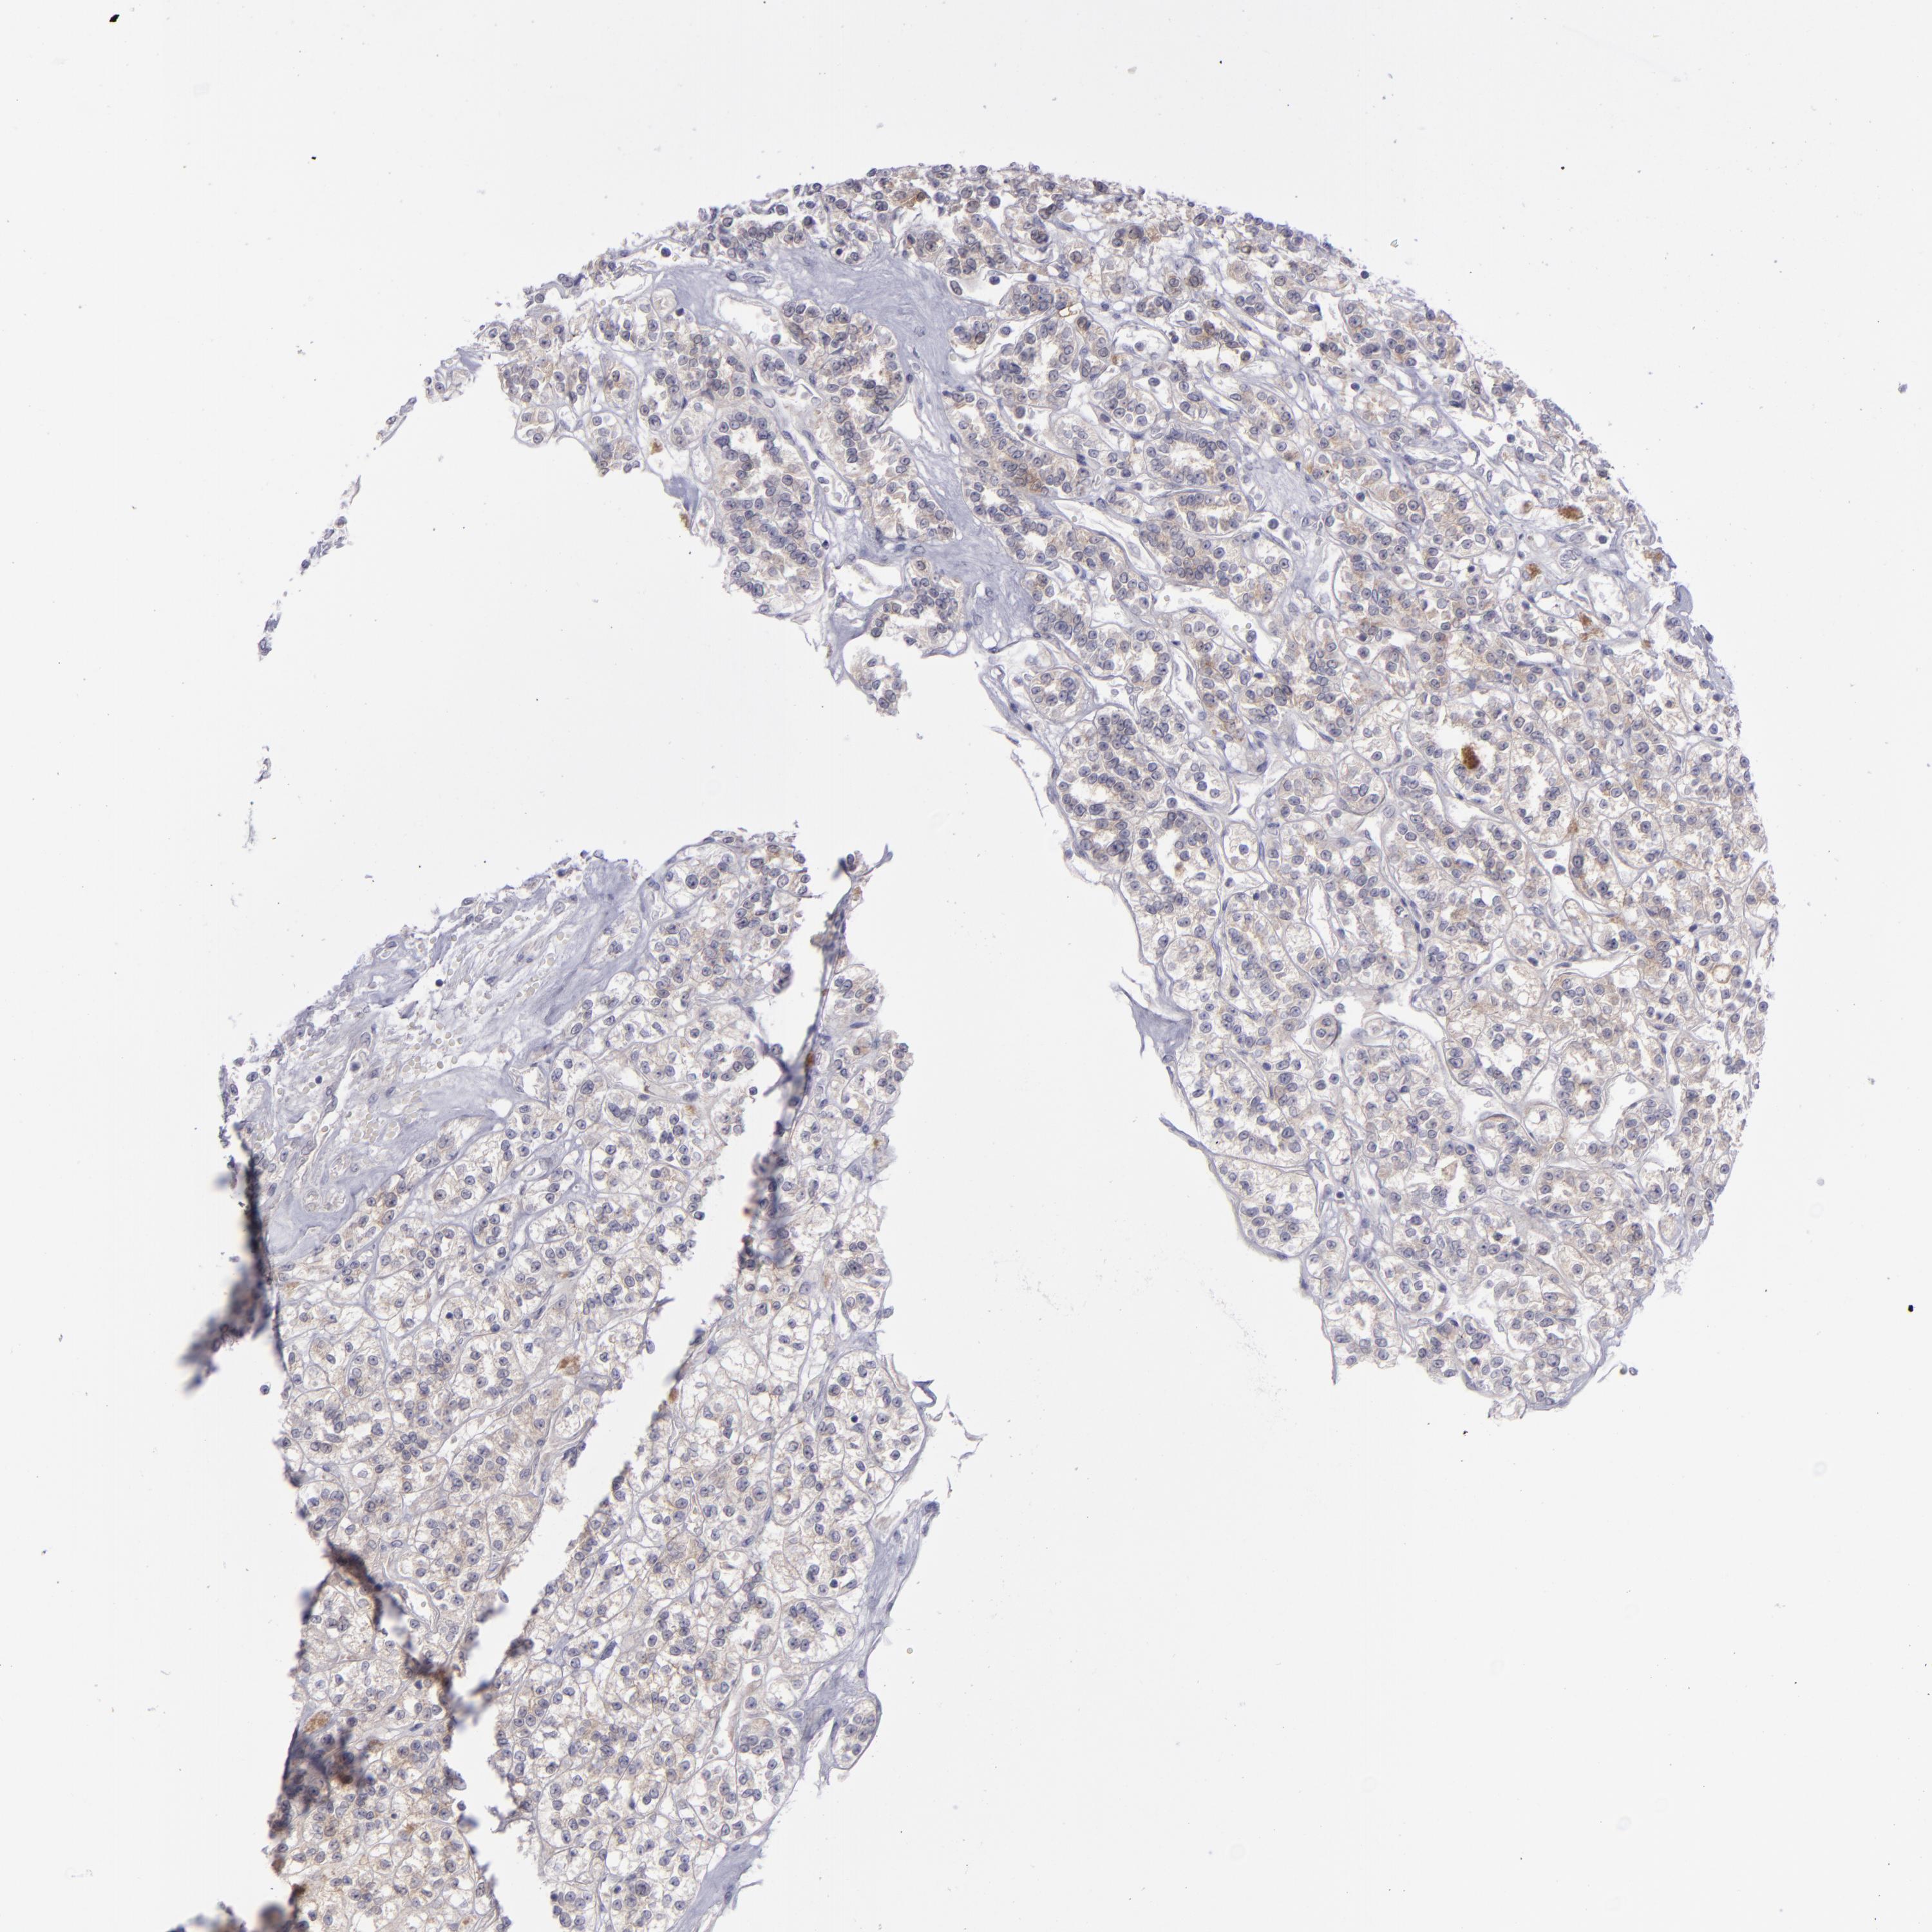

KIDNEY RENAL CLEAR CELL CARCINOMA (VALIDATION) - Interactive survival scatter ploti

The Survival Scatter plot shows the clinical status (i.e. dead or alive) for all individuals in the patient cohort, based on the same data that underlies the corresponding Kaplan-Meier plots. Patients that are alive at last time for follow-up are shown in blue and patients who have died during the study are shown in red.

The x-axis shows the expression levels (FPKM) of the investigated gene in the tumor tissue at the time of diagnosis. The y-axis shows the follow-up time after diagnosis (years). Both axes are complimented with kernel density curves demonstrating the data density over the axes. The top density plot shows the expression levels (FPKM) distribution among dead (red) and alive patients (blue). The right density plot shows the data density of the survived years of dead patients with high and low expression levels respectively, stratified using the cutoff indicated by the vertical dashed line through the Survival Scatter plot. This cutoff is automatically defined based on the FPKM cutoff that minimizes the p-score. The cutoff can be changed by dragging the vertical line or by entering a cutoff value in the square labeled "Current cut-off".

Under the Survival Scatter plot the p-score landscape (black curve; left axis) is shown together with dead median separation (red curve; right axis). Dead median separation is the difference in median mRNA expression between patients who have died with high and low expression, respectively. It is calculated as follows: median FPKM expression of dead patients with high expression - median FPKM expression of dead patients with low expression. This is intended to aid the user in visually exploring custom cutoffs and the associated p-scores and dead median separation.

Individual patient data is displayed and can be filtered by clicking on one or more of the category buttons on the top of the page. Categories describing expression level and patient information include: high, low, alive, dead, female, male and tumor stages. The scale of the x-axis can be toggled between linear and log-scale by clicking on the "x log" button. Mouse-over function shows TCGA ID, patient information and mRNA expression (FPKM) for each patient.

& Survival analysisi

Kaplan-Meier plots summarize results from analysis of correlation between mRNA expression level and patient survival. Patients were divided based on level of expression into one of the two groups "low" (under cut off) or "high" (over cut off). X-axis shows time for survival (years) and y-axis shows the probability of survival, where 1.0 corresponds to 100 percent.

EVPL is not prognostic in Kidney Renal Clear Cell Carcinoma (validation)

Best expression cut offi

Based on the FPKM value of each gene, patients were classified into two groups and association between prognosis (survival) and gene expression (FPKM) was examined. The best expression cut-off refers the FPKM value that yields maximal difference with regard to survival between the two groups at the lowest log-rank P-value. Best expression cut-off was selected based on survival analysis .

When clicking on this number, the vertical dashed line indicating cut-off, the interactive survival plot, and the Kaplan-Meier curve will be adjusted to show results based on the best expression cut-off.

: 6.63

P scorei

Log-rank P value for Kaplan-Meier plot showing results from analysis of correlation between mRNA expression level and patient survival.

N/A

TCGA RNA samplesi

RNA-seq data is reported as average FPKM (number Fragments Per Kilobase of exon per Million reads), generated by the The Cancer Genome Atlas (TCGA) .

Normal distribution across the dataset is visualized with box plots, shown as median and 25th and 75th percentiles. Points are displayed as outliers if they are above or below 1.5 times the interquartile range. FPKM values of the individual samples are presented next to the box plot.

Average pTPM 5.3

Number of samples 100